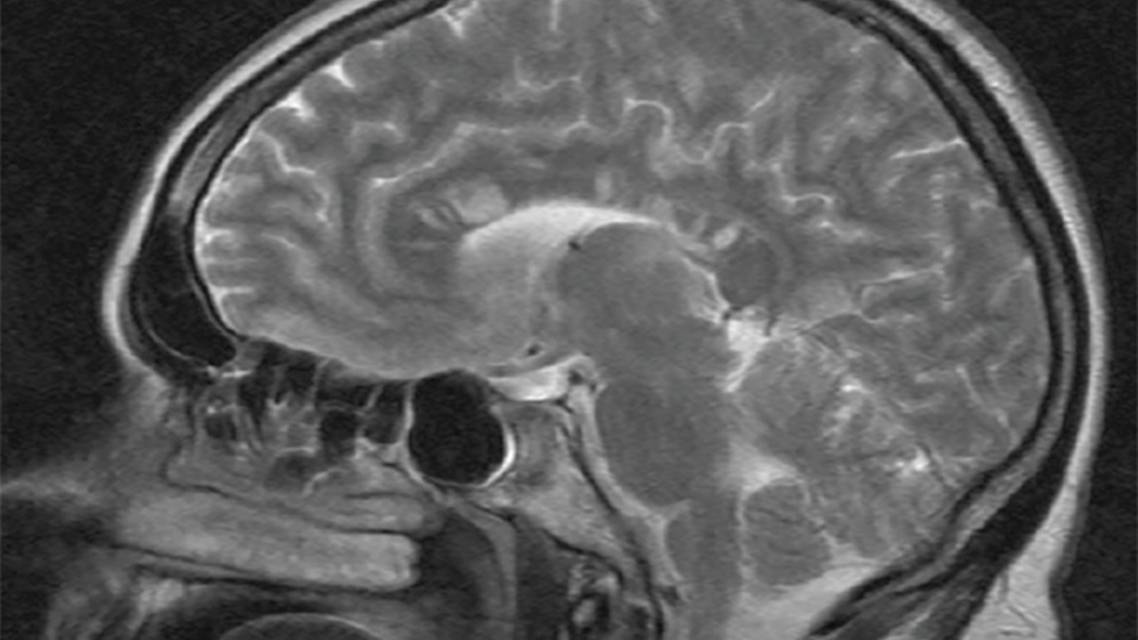

Magnetic Resonance Imaging

Brain MRI is crucial for diagnosis of SuS. Characteristic round snowball lesions in the center of the corpus callosum, are typical for the acute phase of SuS and can be seen best in fluid-attenuated inversion recovery (FLAIR) sequences (Figure 1).18,19 Of note and in contrast, MS lesions are typically located at the undersurface of the corpus callosum rather than in the center. Lesions of the white matter are frequently found in the centrum semiovale and in periventricular or subcortical regions, as well as in the cerebellum or the brainstem.18 Gray matter is affected in 70% of cases, and leptomeningeal contrast enhancement (30%) or contrast-enhancing lesions (70%) can be found in the acute disease phase.18 Diffusion restrictions in the acute phase represent ischemic strokes.20 Diffusion tensor imaging (DTI) demonstrates structural damages of the fiber integrity in the prefrontal cortex and the genu of the corpus callosum.21 On 7 T MRI, lesions in people with SuS are different from lesions of MS in that there is no central vein sign and rarely a hypointense rim.22